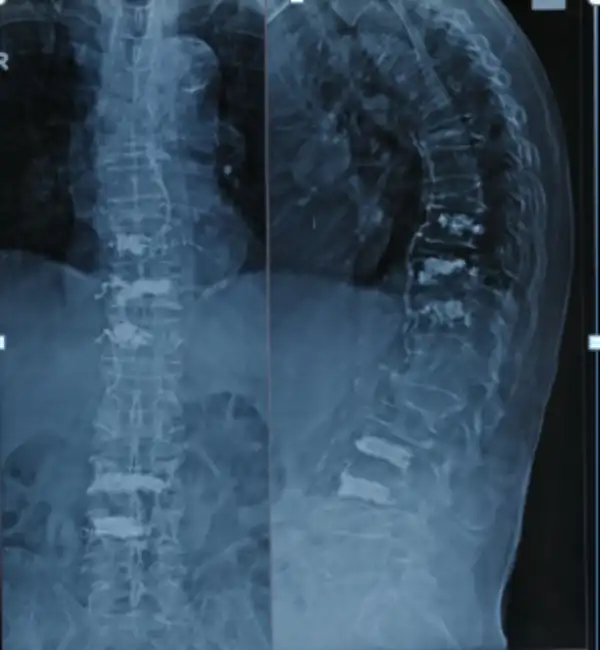

Pre Op X ray Vertebroplasty

Post Op X ray Vertebroplasty